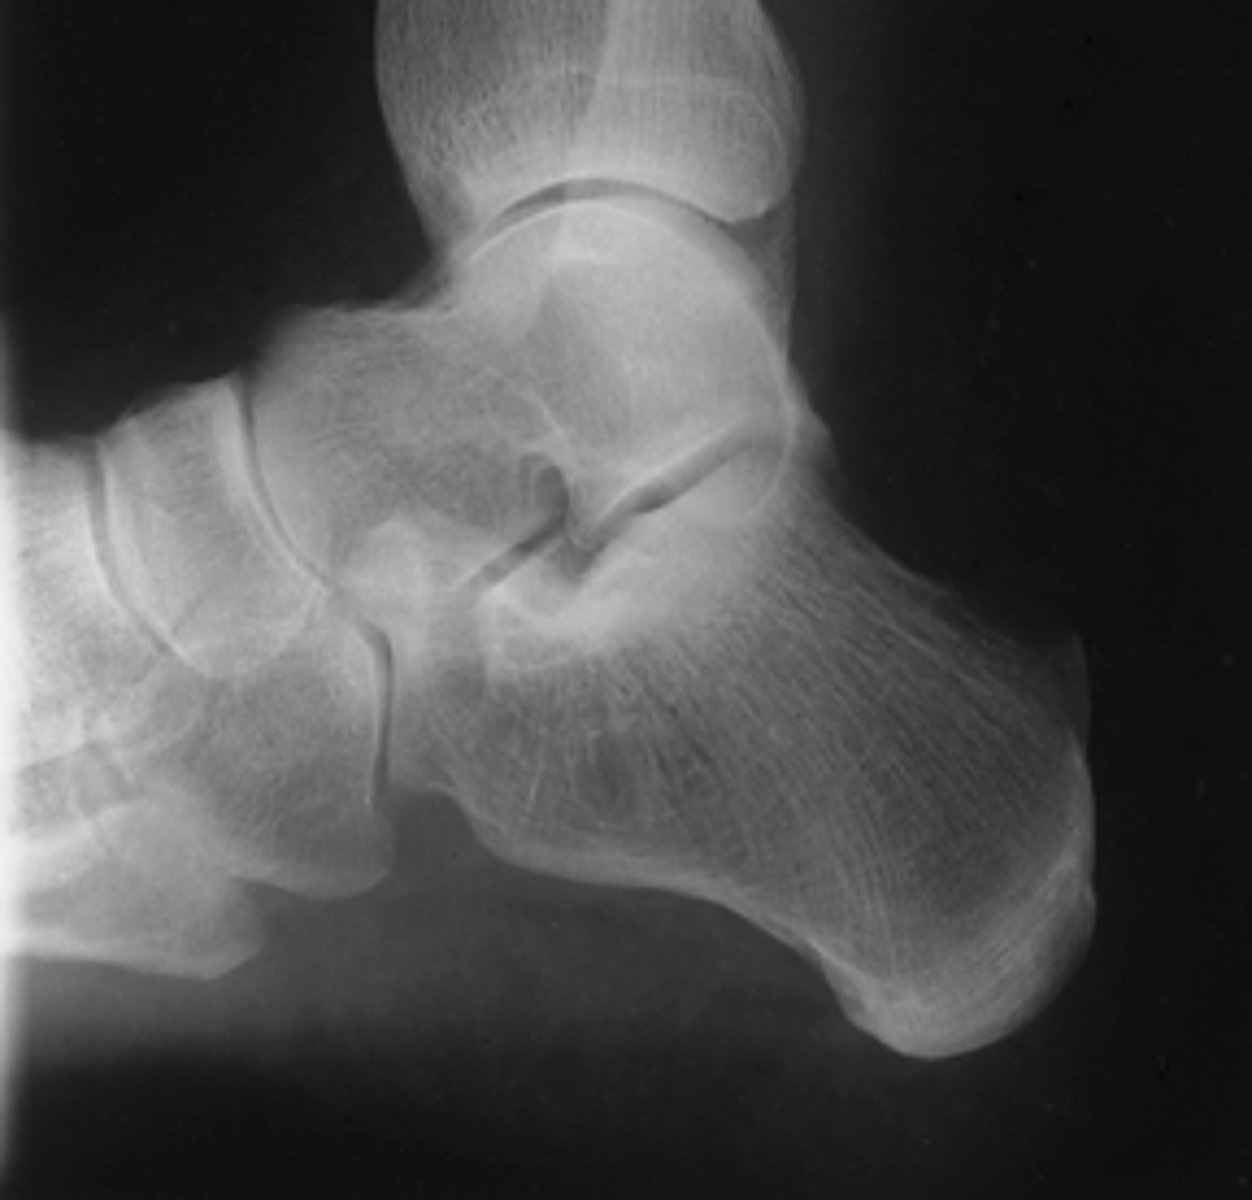

Mediolateral Calcaneus

What projection is this?

Evaluation Criteria Mediolateral Calcaneus

- CR 1 inch (2.5 cm) inferior to medial malleolus

- Calcaneus and talus visualized

- No rotation

- Optimal exposure factors